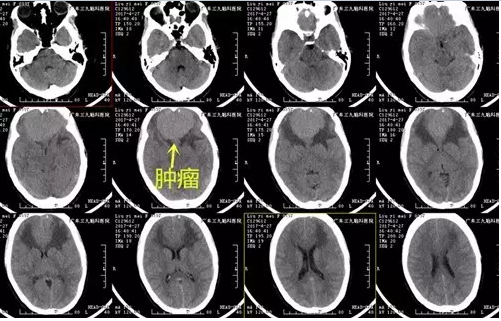

图1:术前CT显示前颅窝一软组织肿块影

图2:术前磁共振提示前颅窝底一团块占位性病变,大小约5.5×6.5×3.7cm